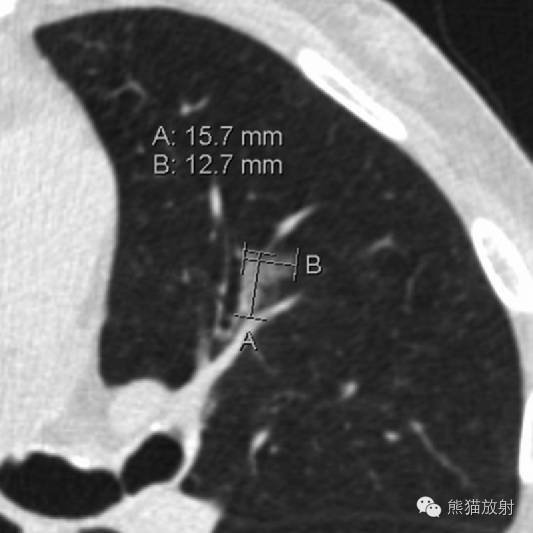

61岁男性,舌段非实性(磨玻璃)结节,平均直径约14mm。(Lung-RADS 2)